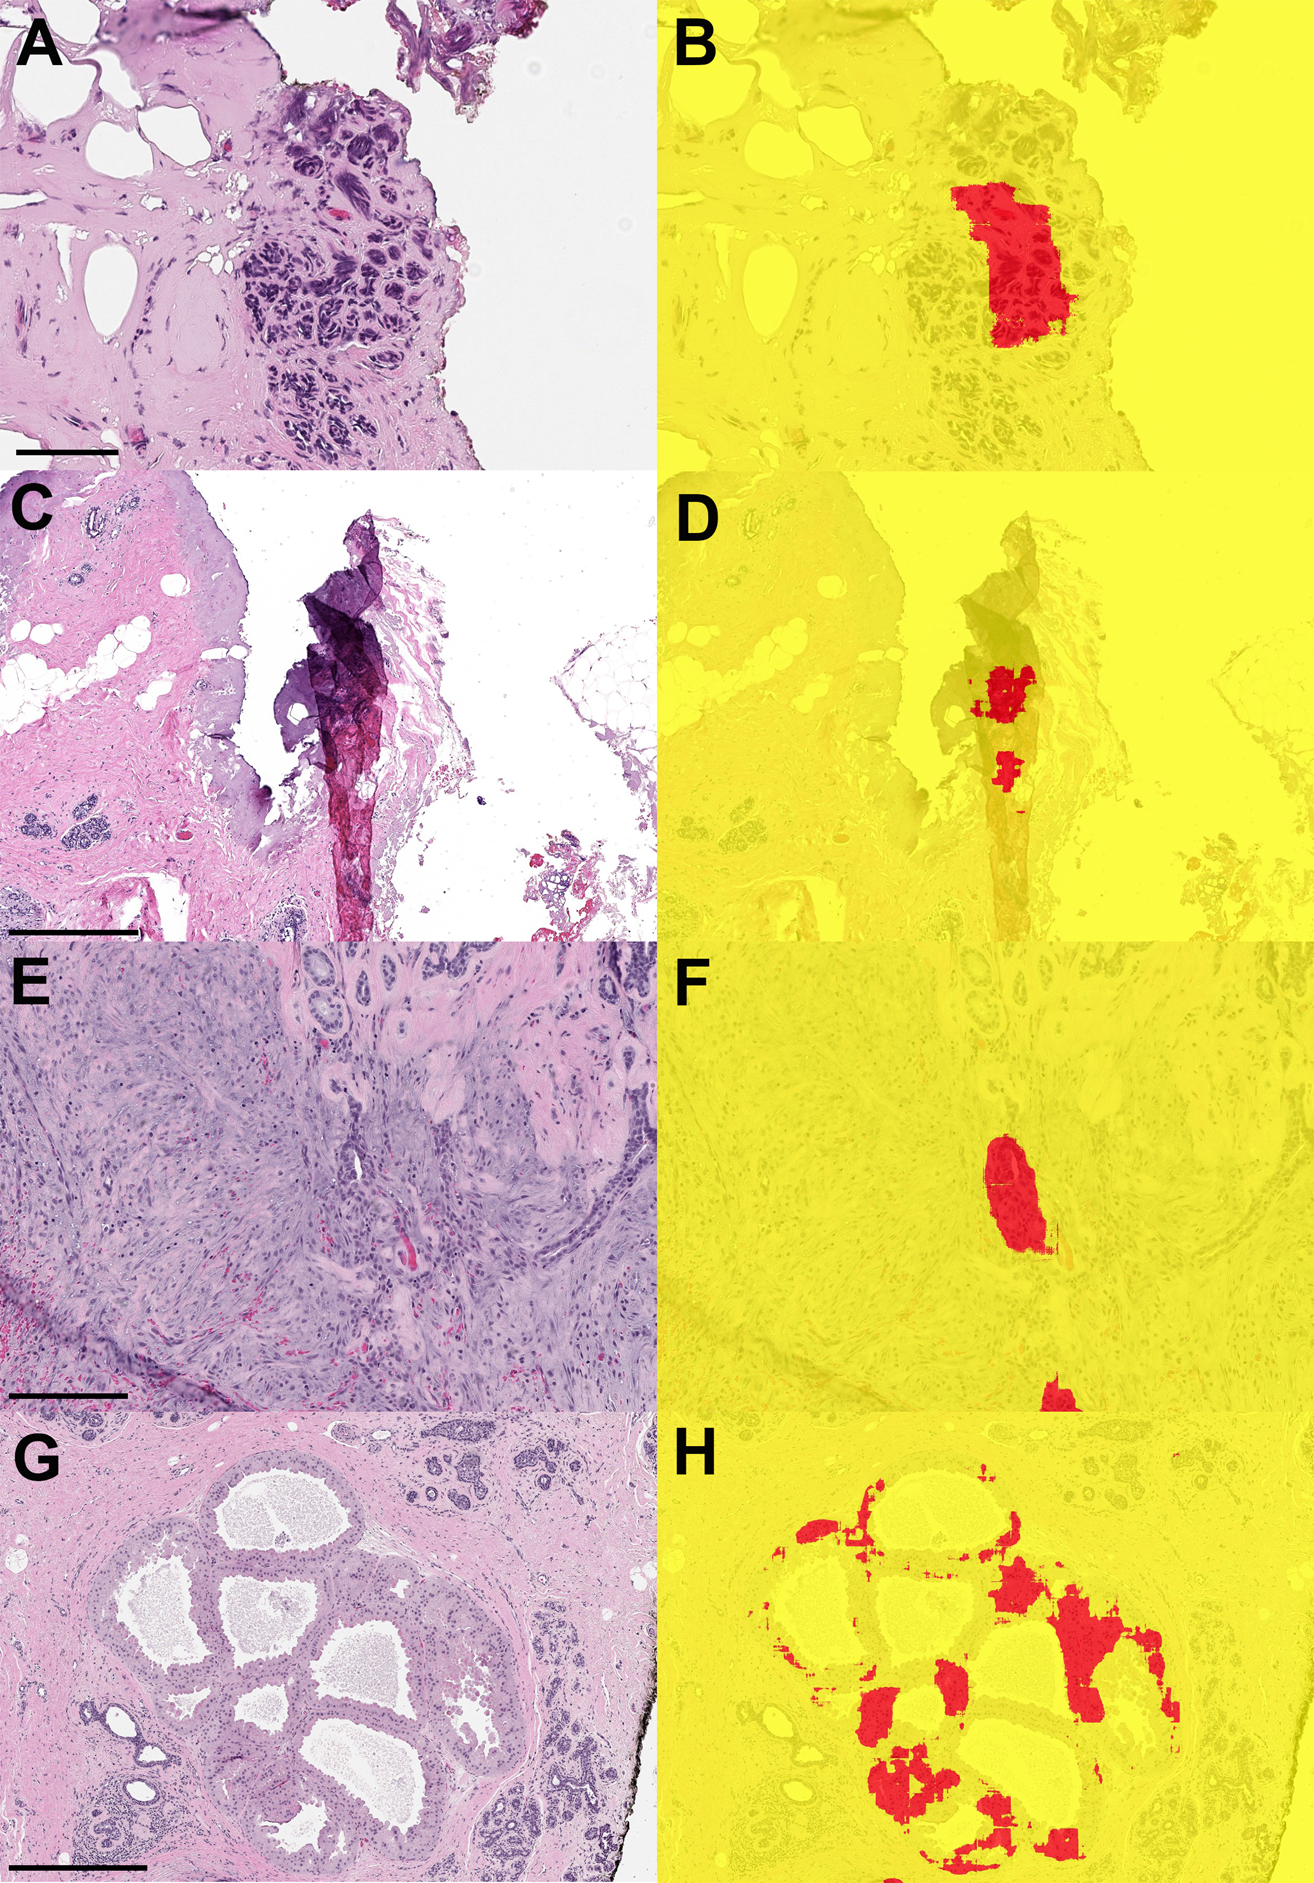

Fig. 7: Examples of whole slide images from benign margin specimens that were falsely classified as positive by the machine learning model.

A, B Benign lobule with cautery artifact ((A): scale bar = 0.1 mm). C, D Fold in tissue led to incorrect classification with the model ((C): scale bar = 0.5 mm). E, F Biopsy site with reactive epithelial changes ((E): scale bar = 0.2 mm). G, H Apocrine metaplasia incorrectly segmented as carcinoma ((G): scale bar = 0.5 mm).